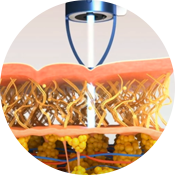

여드름 압출

여드름 압출은 주위 피부에 상처를 입히지 않고 위생적으로

피부의 염증과 면포만 제거하는 피부관리입니다.

압출 전 사전 관리로 충분히 모공을 열어주고

자국, 흉터 없이 매끈하게 여드름을 압출합니다.

- 피부의 손상을 최소화하면서 염증과 면포를 제거

- 상처가 덧나거나 감염되지 않도록 철저한 위생관리

스킨 스케일링

피부의 가장 바깥층에 있는 불필요한 각질을 제거하고

각질 제거로 막혀 있던 모공을 열어주어 피지 배출을 원활하게 합니다.

모공 속에 쌓여있는 피지를 녹여 과도한 피지를 감소시키고,

염증을 감소시켜 여드름 개선에 효과적입니다.

- 불필요한 각질 제거 및 피지 배출, 염증 감소

- 모공 속 노폐물까지 제거하여 모공 개선, 여드름에 효과적